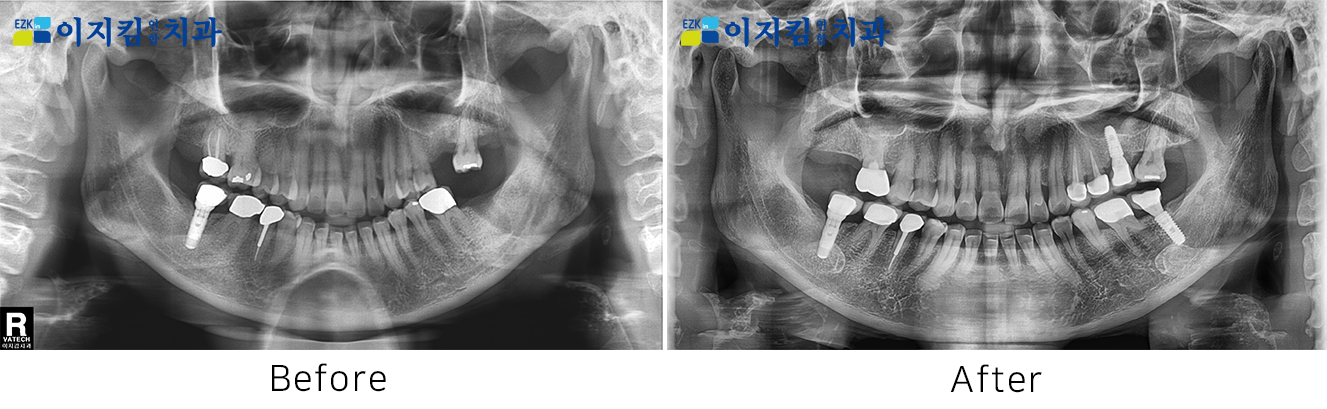

ÀÓÇöõÆ® Àü ¡¤ ÈÄ »çÁø

[

Á¶È¸¼ö : 3163

]